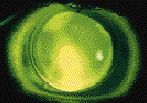

Toric RGP lenses are generally not needed, even if keratometry and corneal topography show that the patient has large amounts of corneal "astigmatism." This is usually not true astigmatism, but is caused by the distorted surface. The only way these instruments can express the irregularity is by yielding astigmatic numbers (Fig. 4). If spherical RGP lenses seem to be unstable because of peripheral corneal toricity, back toric designs can be used. It's possible to visualize peripheral toricity by looking for a differential amount of mid-peripheral and peripheral clearance in the vertical and horizontal meridians (Fig. 5). If it is determined that the patient needs a back toric to improve the fit characteristics of the RGP lens, then an SPE bitoric can be utilized.

FIG. 4: Corneal topography of a keratoconus patient. Note the irregular

topography with inferior steep zone. Also note the simulated "K" readings that

indicate 3.92D of corneal astigmatism

FIG. 5: Fluorescein pattern of a rigid lens on a keratoconic cornea. Note

the excessive peripheral clearance inferiorly and minimal peripheral clearance nasally and

temporally. This demonstrates peripheral corneal toricity.